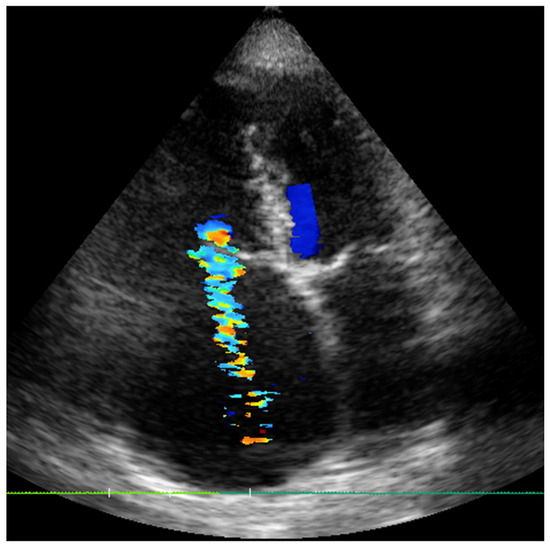

2.1. Case 1

2.2. Case 2

2.3. Case 3